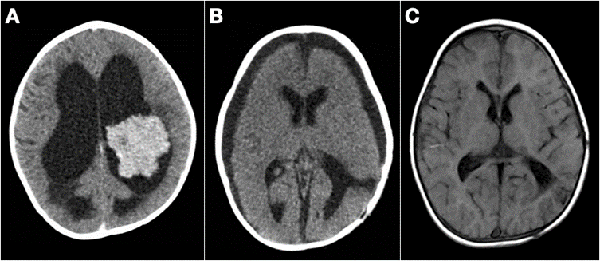

Figura 5: Tumores agresivos. A) Paciente de 8 meses de vida, sexo masculino, presentó irritabilidad, macrocefalia y somnolencia. TC de cerebro con contraste EV donde se observó imagen en región pineal que se extiende al tercer ventrículo. Se realizó cirugía de exploración, exéresis parcial, anatomía patológica informó pineoblastoma, paciente falleció a los 5 meses por progresión de la enfermedad. B) Paciente de 2 meses de vida, sexo masculino, consultó por deterioro progresivo del sensorio. TC de cerebro con contraste EV que evidenció lesión centroencefálica e hidrocefalia obstructiva. Se realizó cirugía de exploración de lesión, con colocación intraquirúrgica de drenaje ventricular al exterior. Anatomía patológica informó tumor embrionario indiferenciado. Paciente falleció a los 14 días por progresión de enfermedad. C) Paciente de 19 meses de vida, sexo femenino, consultó por vómitos a repetición. IRM de cerebro con contraste EV que mostró tumor supratentorial intraventricular con realce homogéneo con el contraste EV. Se realizó cirugía de exploración, con exéresis parcial por el intenso sangrado. Anatomía patológica informó carcinoma de plexos coroideos. Paciente fallece a los 3 meses.

Figura 7: A) Paciente de 13 meses, sexo masculino, consultó por alteraciones en la motricidad. TC de cerebro con contraste EV que evidenció lesión intraventricular que realza homogéneamente e hidrocefalia, se colocó DVE previo a cirugía de exéresis tumoral. B) TC de cerebro luego de cirugía, diagnóstico de papiloma de plexos coroideos, se retiró el DVE a las 48 hs. TC de cerebro de control al año con colecciones subdurales crónicas. Se decidió conducta expectante de las mismas. C) IRM de cerebro control a los 3 años, sistema ventricular de tamaño normal, corticotomía cerrada. Paciente sin secuelas neurológicas.